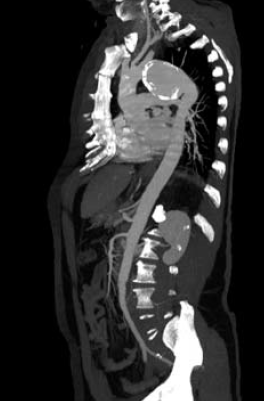

4. ábra.

4. sorszámú betegünk DSA felvétele az isthicus aorta III. stádiumú tompa aorta sérülését mutatja.

4. 22 éves fiatal ffi motorbaleset során szenvedett el mellkasi zúzódást, ami a típusos szakaszon álaneurysma képződéssel társult. A diagnózist mellkas röntgenfelvételek és DSA biztosította. Felkartörés rögzítést követően stabil morfológiai állapotban, 20 nappal a sérülés után stentgraft beültetést végeztünk subclavia transpositio nélkül (4.,5. ábra).